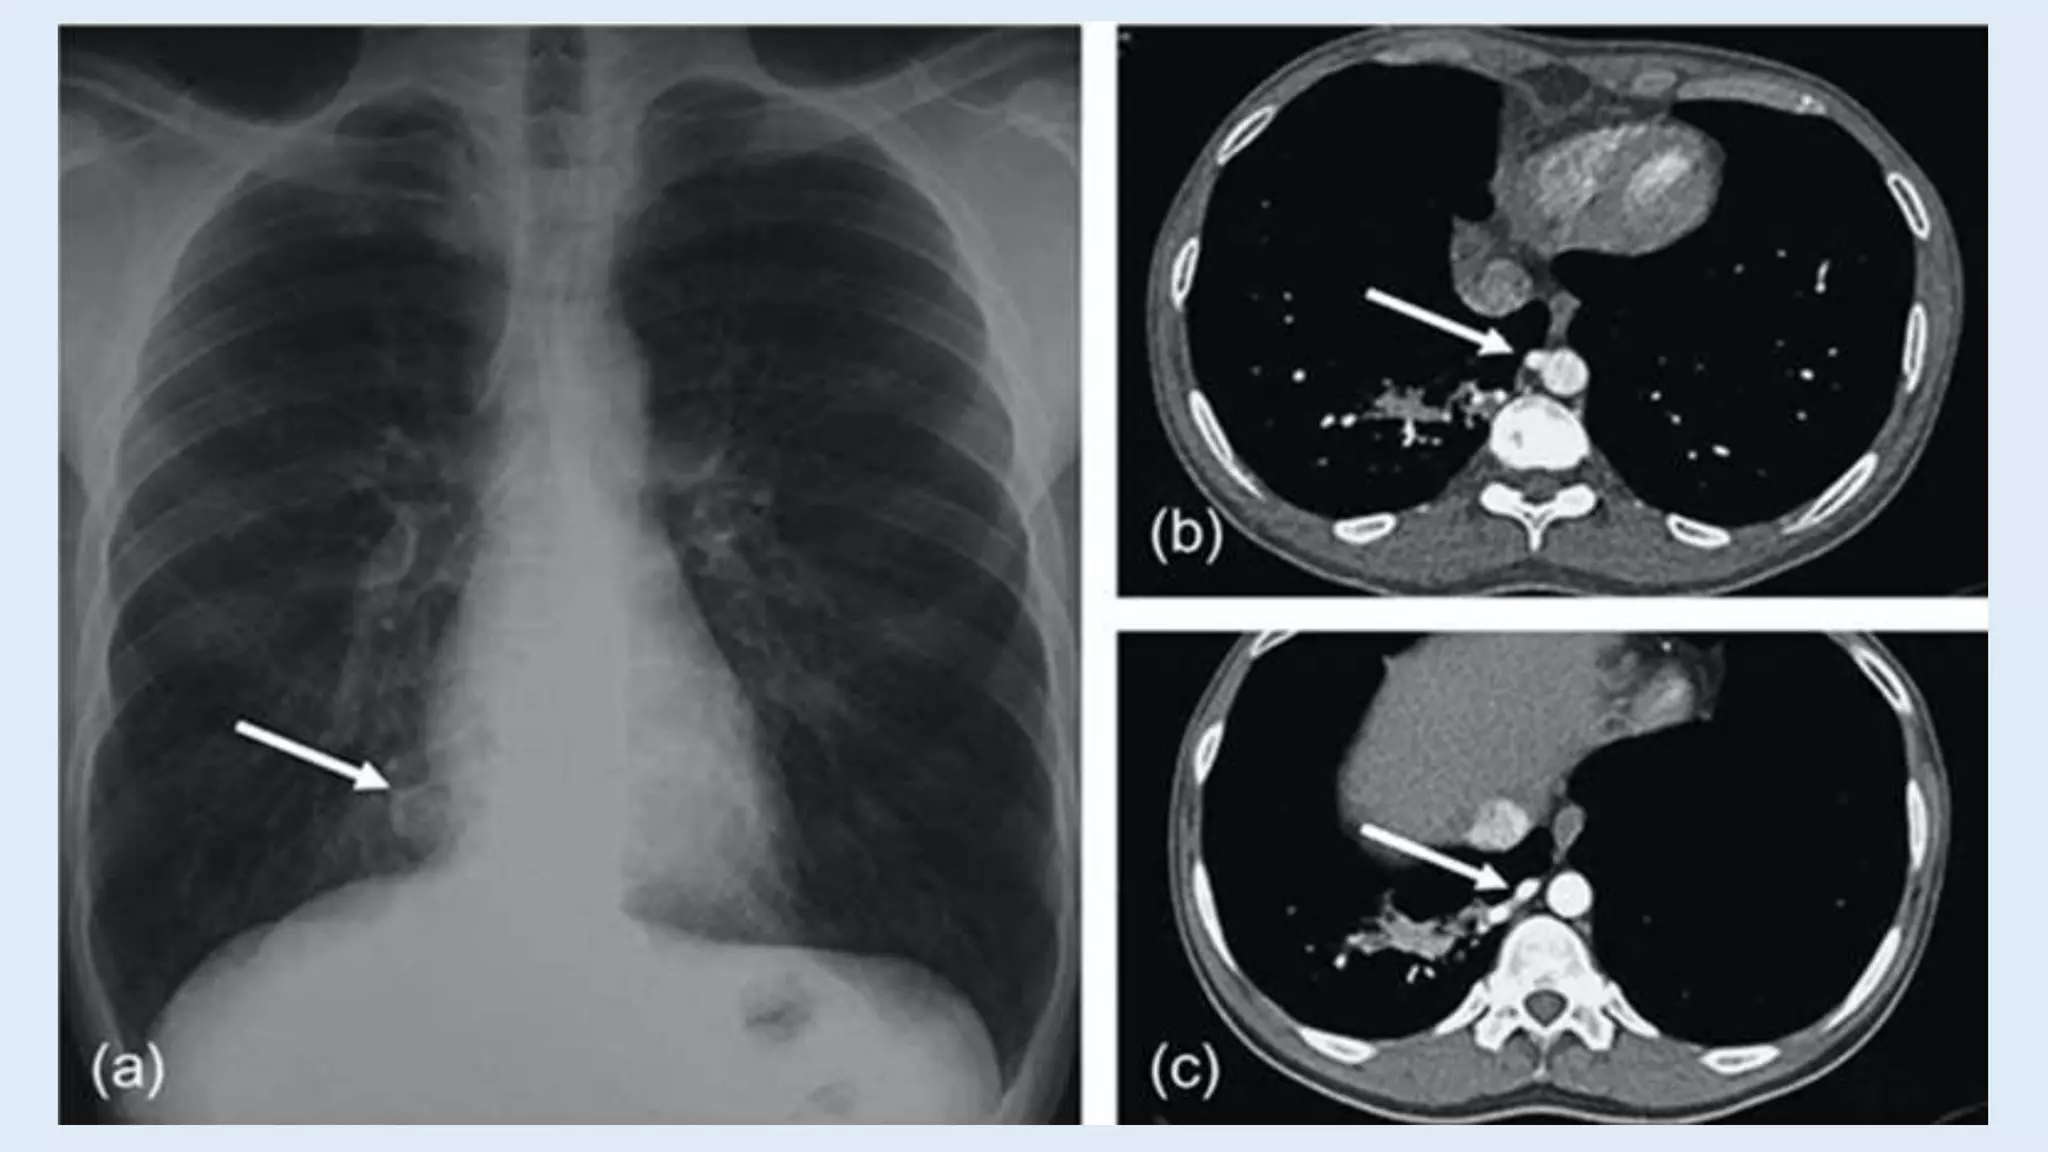

• Chest Radiograph:

Sequestrations typically appear as a uniform dense mass within the

thoracic cavity or lung parenchyma.

Recurrent infections in ILS can lead to cystic areas within the mass.

Air-fluid levels in case of bronchial communication

Computed tomography (CT)

• Most common appearance is a solid mass that may be

homogenous or heterogenous, sometimes with cystic

changes.

• Less frequently, a large cavitary lesion with an air-fluid level.

• Emphysematous changes at the margin of the lesion.

Post Natal Evaluation •Chest Radiograph: Sequestrations typically appear as a uniform dense mass within the thoracic cavity or lung parenchyma. Recurrent infections in ILS can lead to cystic areas within the mass. Air-fluid levels in case of bronchial communication

Computed tomography (CT) •Most common appearance is a solid mass that may be homogenous or heterogenous, sometimes with cystic changes. • Less frequently, a large cavitary lesion with an air-fluid level. • Emphysematous changes at the margin of the lesion.